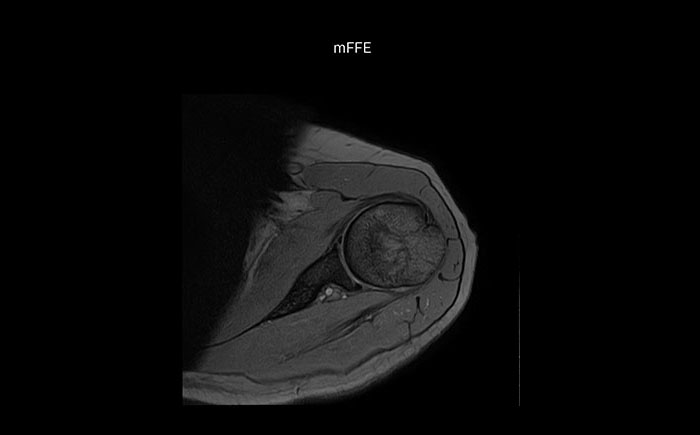

Shoulder MRI with high quality, large coverage

The Prodiva shoulder coil is very flexible and has large coverage, which makes good positioning easier, and that contributes to the superb image quality and high SNR that we get in our shoulder exams.

Scan time 2:55 min, FOV 160 mm,

acq voxels 0.55 x 0.83 x 3.0 mm.

Scan time 4:19 min, FOV 160 mm,

acq voxels 0.55 x 0.80 x 3.0 mm.

Scan time 2:50 min, FOV 160 mm,

acq voxels 0.70 x 0.99 x 3.0 mm.

Shoulder MRI with high quality, T2 SPIR

Shoulder MRI with high quality, mFFE

Shoulder MRI with high quality, STIR TSE